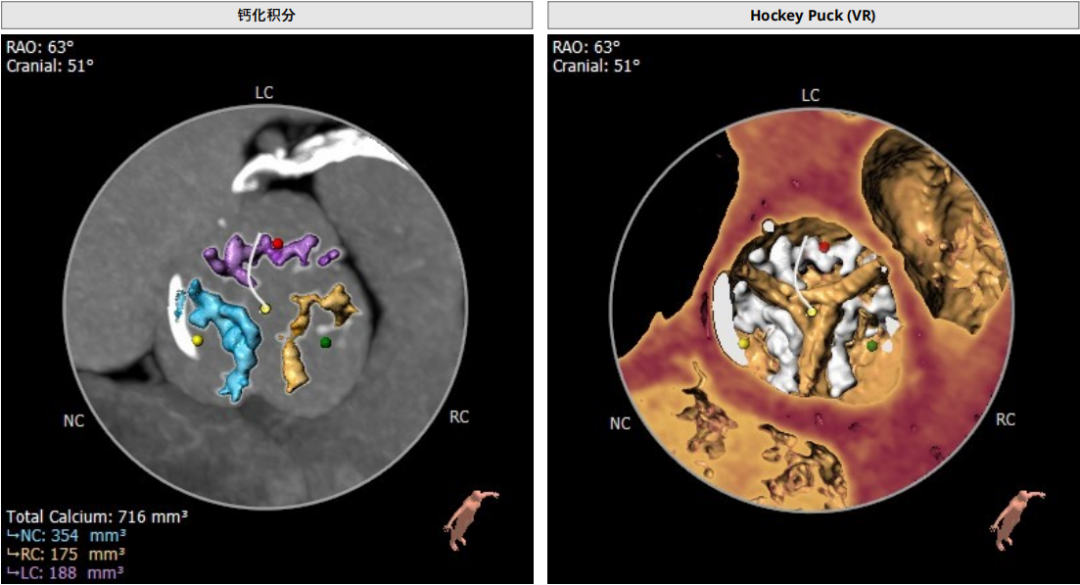

钙化积分及分布

三叶瓣,重度钙化,钙化主要分布在瓣叶游离缘,法式窦结构较大,双冠高度较高,升主动脉未见明显扩张,心脏角度40°,左室大小可,心肌肥厚,主动脉弓部走行较平缓,主动脉弓部可见钙化,过弓轻柔谨慎,以右侧股动脉为主入路。